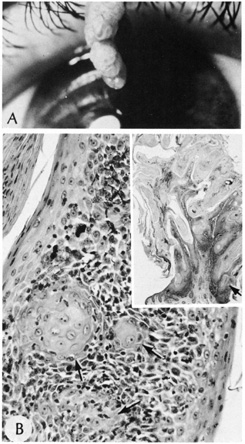

Histologically, inverted follicular keratoses are exoendophytic and symmetric. There is a bulbous proliferation of keratinocytes showing abundant eosinophilic cytoplasms into the dermis. Often, the stratum corneum is parakeratotic and contains neutrophils, serum, and red blood cells. A characteristic feature, which is also shared with irritated seborrheic keratoses, is the presence of squamous eddies, which are whorls of eosinophilic keratinocytes arranged in an onion-peel fashion (Fig. 26). Some authors believe that inverted follicular keratoses are really irritated seborrheic keratoses or verrucae with squamous eddies.

Fig. 26. Inverted follicular keratosis. A. Clinical appearance. B. Inset shows hyperkeratotic papillomatous lesion shown under high magnification, (arrow main figure). Note: acantholytic squamous cells surrounding squamous eddies (arrows). (Modified from Sassani JW, Yanoff M: Inverted follicular keratosis. Am J Ophthalmol 87:810, 1979; and Scheie HG, Yanoff M, Sassani JW: Inverted follicular keratosis mimicking malignant melanoma. Ann Ophthalmol 9:949, 1977.)

The characteristic histologic features are a cupshaped invagination filled with keratinous material and acantholytic, dyskeratotic cells. Villi of dermal papillae project into the base of the crater and are lined by a single layer of basal cells. Corps ronds, which are dyskeratotic cells containing a pyknotic nucleus surrounded by a clear halo, are seen in the granular layer at the entrance of the invagination (Fig. 27). The presence of acantholytic dyskeratosis with corps ronds is reminiscent of Darier's disease, but warty dyskeratoma is believed to represent a distinct cutaneous tumor with histologic resemblance to Darier's disease.

Fig. 27. Warty dyskeratoma. A. Scanning magnification shows a bulbous endophytic proliferation with acantholysis. B. High magnification shows dyskeratotic keratinocytes with a pyknotic nucleus (corp ronds).